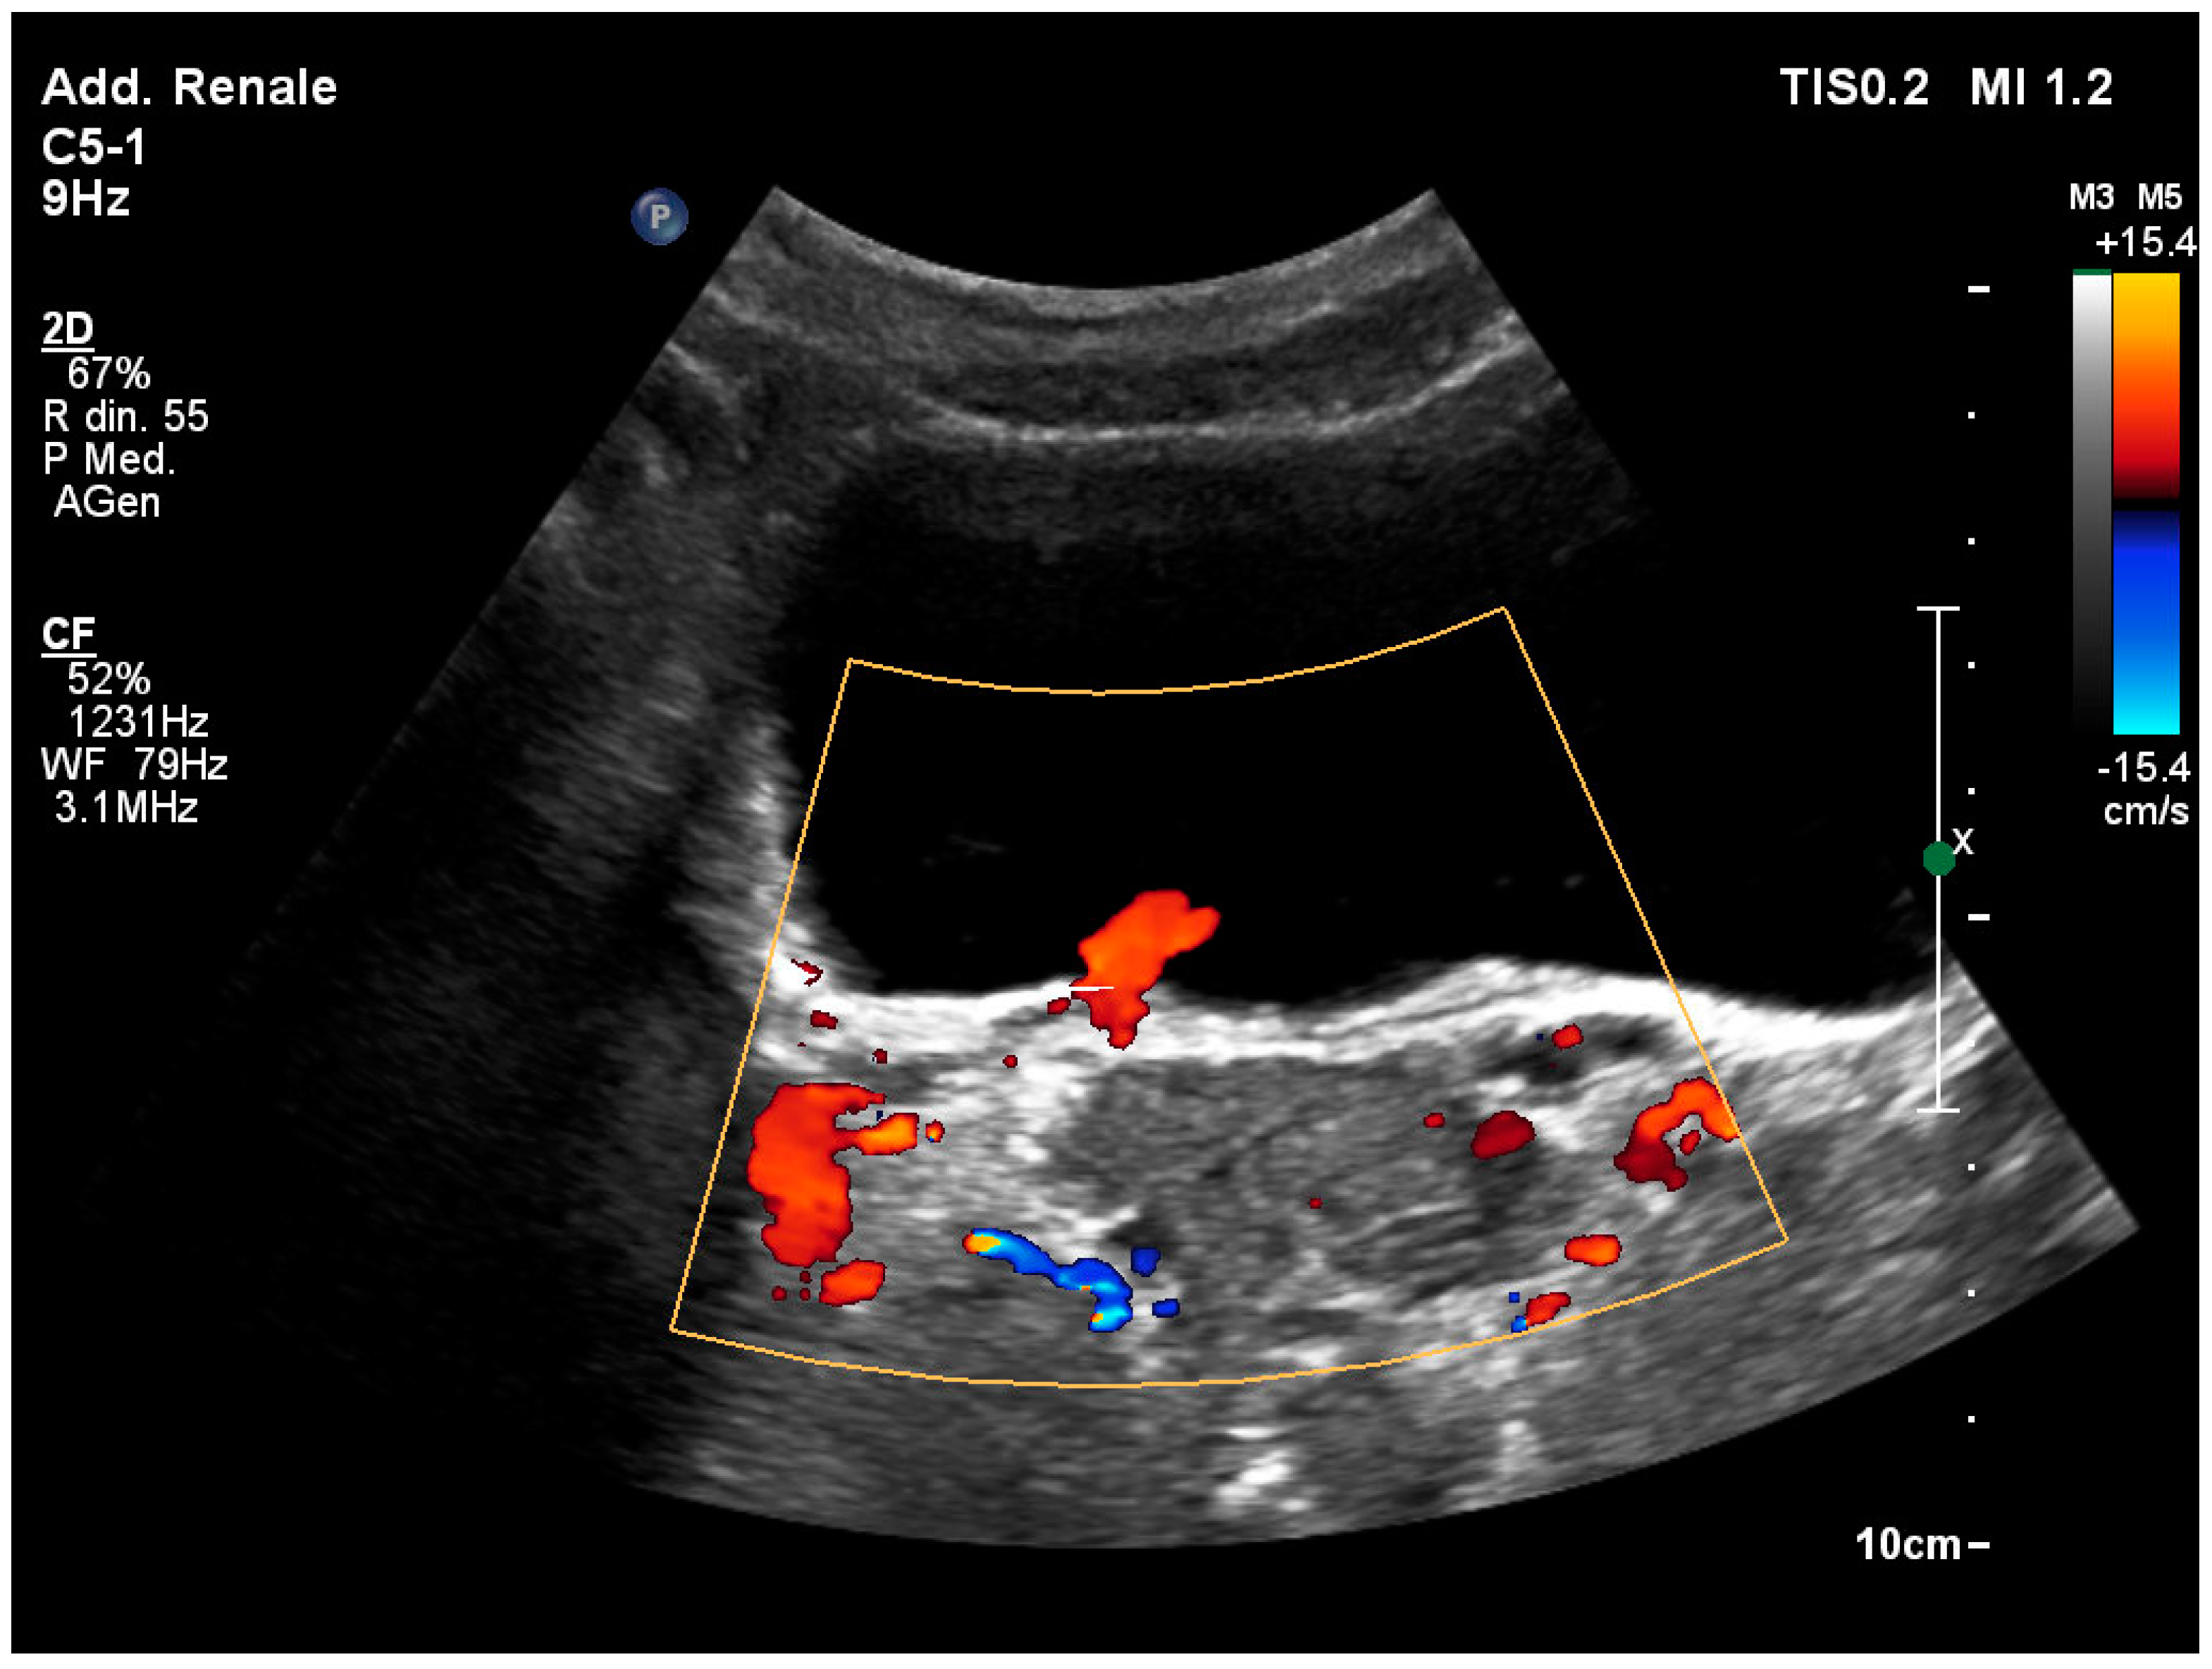

3.5. The “Twinkling” Artifact

3.6. The “Swinging Kidney” Sign

3.7. Identification of the Ureteral Jet